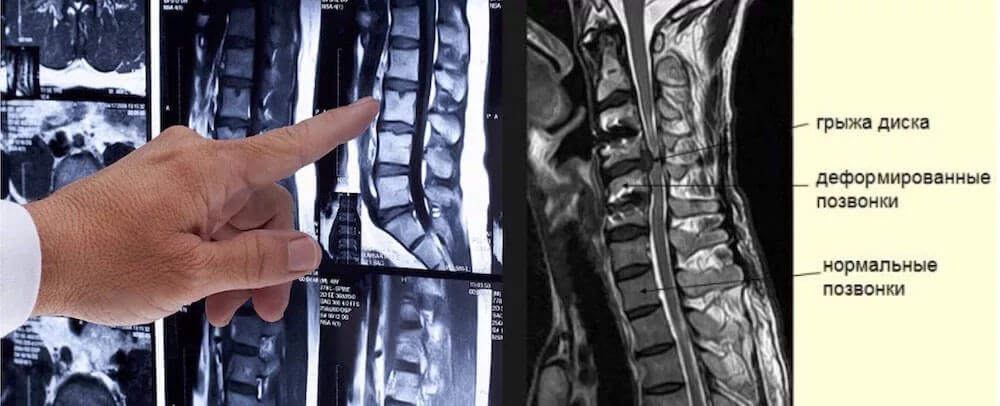

Еще более сильные боли, трудность с движением. Каждый поворот головы способен стать причиной приступа головокружения, тошноты. Нарушения кровоснабжения мозга приводит к общей вялости, быстрой утомляемости, нарушению концентрации внимания, хрящевая ткань истончается, позвонки смыкаются, фиброзное кольцо полностью разрушается, формируется межпозвонковая грыжа.

При постановке первичного диагноза "остеохондроз шейного отдела позвоночника" врач направит пациента на дополнительные исследования. Среди которых наиболее эффективным считается МРТ, так как способен диагностировать начальные изменения. Следующими по эффективности следуют компьютерная томография, рентген. Для проверки состояния мягких тканей используется УЗИ. При подозрении повреждения кровеносных сосудов, врач может выписать направление на дуплексное сканирование сосудов. Возможно потребуется консультация кардиолога, поскольку некоторые симптомы схожи с признаками стенокардии и ишемической болезни сердца.